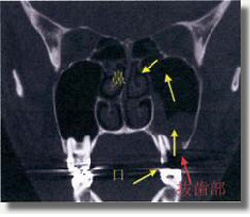

上顎洞底に歯の根の先が突出しており、上顎洞粘膜(黄色の矢印)が腫れて上顎洞炎を引き起こしている。